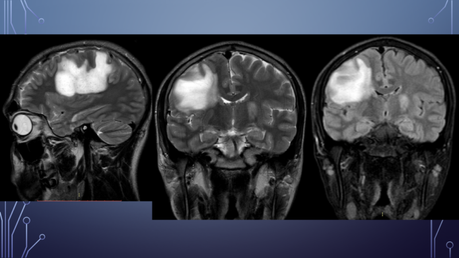

PA: Inicia hace 5 meses con amnesia, cefalea generalizada la cual empeora con el ejercicio, agregándose parálisis facial izquierda por lo que acude con neurólogo privado solicitando TC y posteriormente RM.

El paciente es diagnosticado con EM.